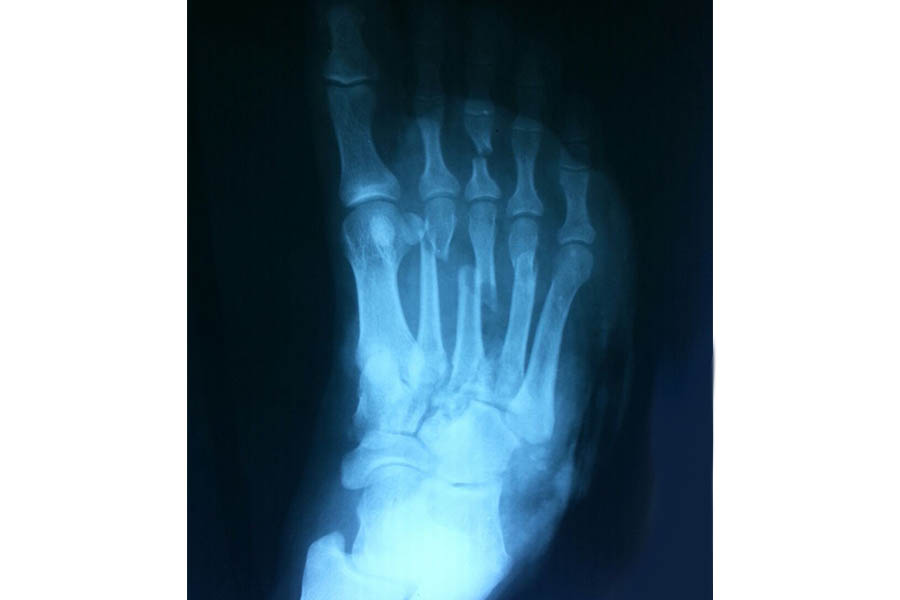

Trauma